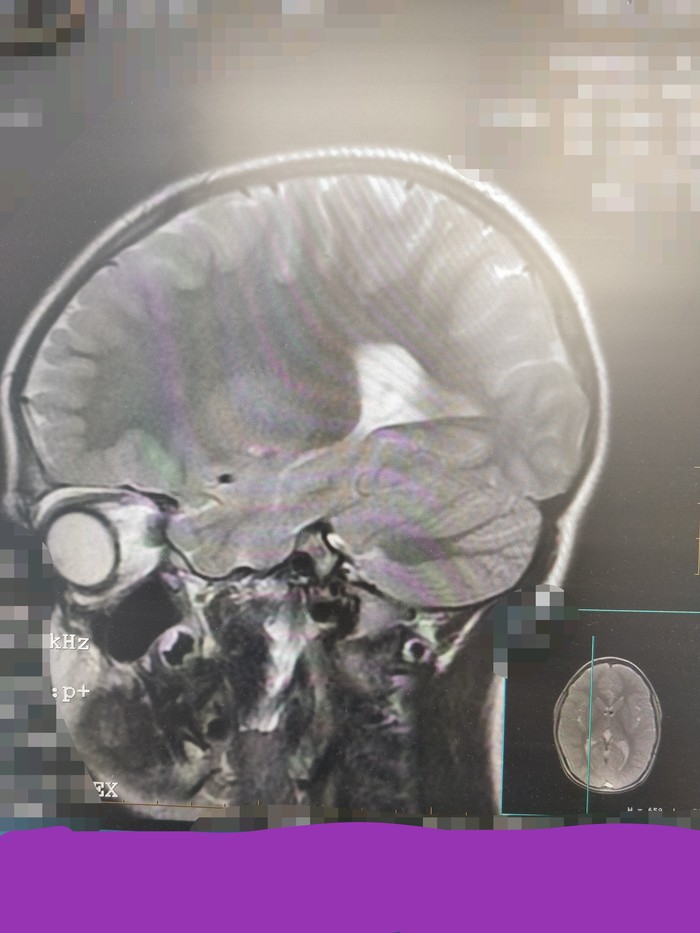

4. Ну а это, собсна, ваш покорный слуга с заложенным носом)

Если данная рубрика зайдет, буду продолжать. На срезах малых тазов тоже бывает интересно)

Пациенты подписывали согласие на анон участие в образовательном процессе, ну а от образовательного до развлекательного рукой подать)